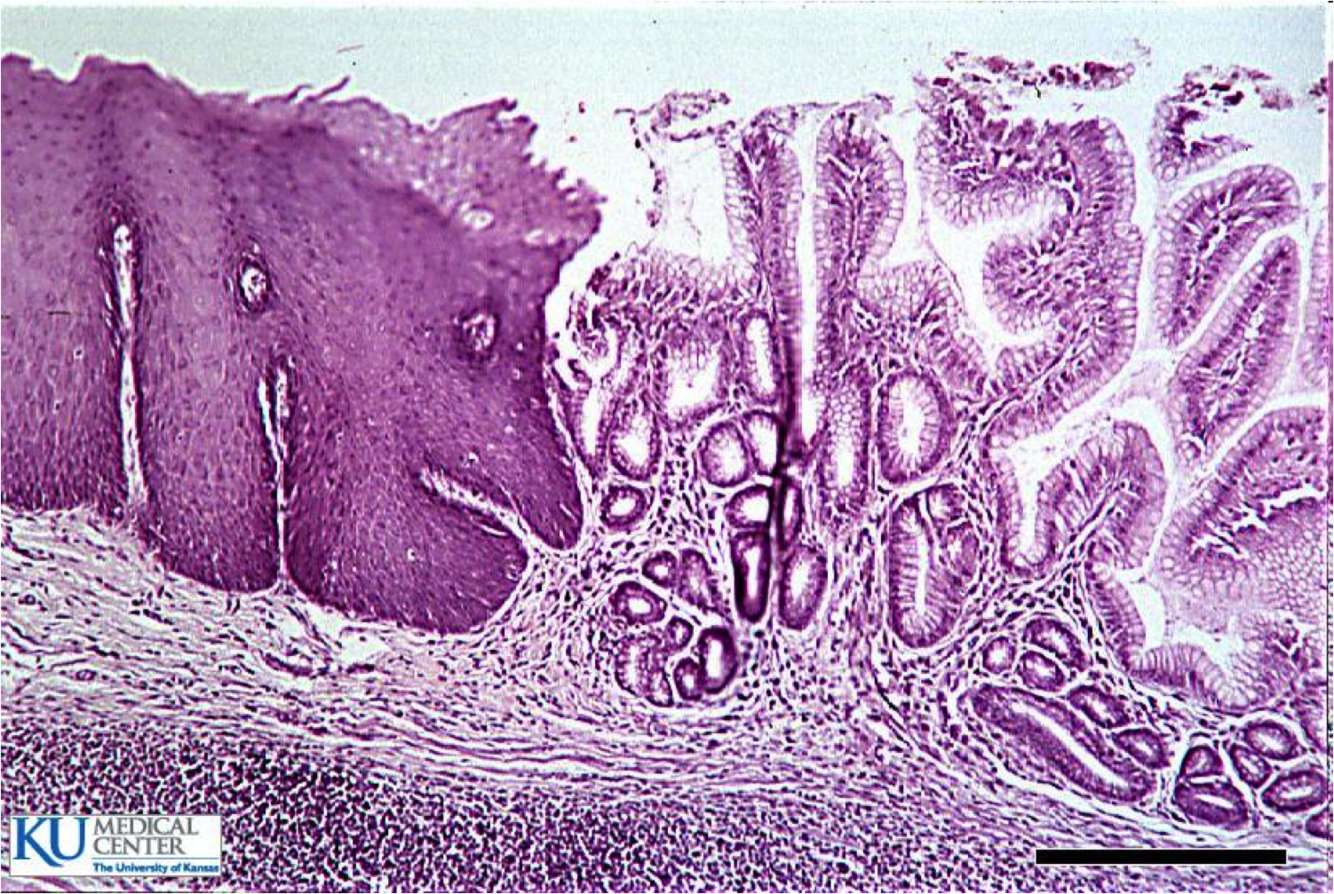

distal 2/3=smooth muscle - GE junction (where rugal folds begin)

- Z-line (squamocolumnar junction): mucosal junction of squamous and columnar epithelium, may not correspond to GE junction when columnar metaplasia has occured

normal gastroesophageal junction

stratified sqaumous of esophagus

simple columnar of gastric cardia

Barrett’s esophagus

Endoscopically recognizable columnar metaplasia of the esophageal mucosa that is confirmed pathologically to have intestinal metaplasia, the latter defined by goblet cells

Both the endoscopic and pathologic components should be present to establish BE.

Barrett’s esophagus: columnar metaplasia (intestinal metaplasia)+goblet cells